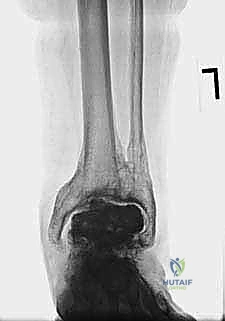

- Plain Radiographs: These are your first line. Malleolar fractures can be subtle or obvious.

- Obvious Fractures: Visible at the level of the prosthesis, generally at its apex or superior corners. In iatrogenic cases, they often occur at the superior saw cut line on the tibia, where the sagittal saw may have violated the malleolus. Significant distraction during the index procedure on osteoporotic bone can create avulsion fractures.

- Subtle Fractures: Often delayed in appearance, presenting as periosteal reactions at the medial malleolus proximal to the prosthesis. These typically indicate an unbalanced prosthesis placing uneven load or compression across the malleoli.